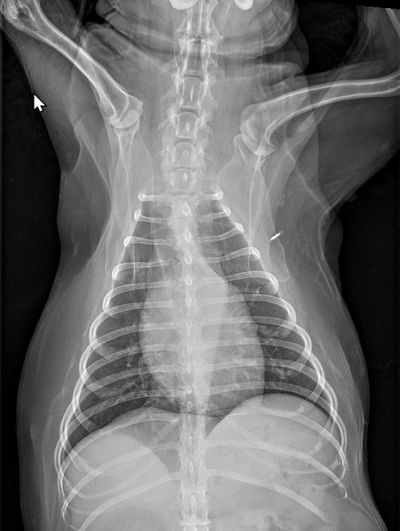

1. 評估心臟輪廓

當犬貓有心臟疾病,並造成腔室擴大,X光影像會顯示心臟輪廓變大或形狀改變。犬隻二尖瓣膜性疾病常見左心房膨大、心臟整體變大而氣管抬升;貓咪肥厚性心肌病常見仰躺照的心臟呈現愛心形。

3. 評估血管粗細

心臟疾病造成肺部血管灌流量改變,在X光影像會顯示肺部血管粗細改變。例如感染心絲蟲時,可能會看到右心擴大,及肺動脈變粗甚至變扭曲。